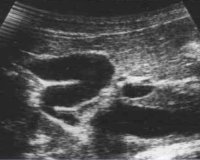

Перегиб желчного пузыря: причины и фото диагностики